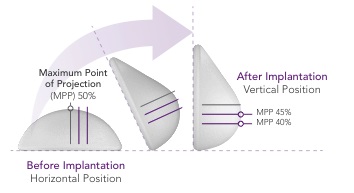

We launched Motiva Implants commercially in October 2010, and to date we have sold approximately 1.4 million units in various countries outside the United States. Motiva Implants incorporate a number of proprietary features that we believe contribute to Motiva Implants’ favorable safety profile as well as a natural appearance and feel. Our latest generation of Motiva Implants utilize our proprietary Ergonomix design, a round base implant that

responds to gravity by shifting its maximum point of projection, offering the projection of a shaped implant without the malpositioning and rotation issues frequently associated with shaped implants. Furthermore, our ProgressiveGel family of silicone gel rheologies consists of four highly purified biocompatible gels with specific visco-elastic properties that we believe enables Motiva Implants to respond to the patient’s motion in ways that more closely mimic the appearance, feel and movement of natural breast tissue. Our catalog includes over 1,000 product variations, with round, oval and anatomical shapes, two different surfaces and volumes ranging from 105cc to 1,050cc, making it a wider range of options than those offered by our major competitors.

In addition to the safety advantages, our ProgressiveGel family provides for movement characteristics that resemble natural breast tissue. Our later generation Ergonomix products further mimic natural tissue, with a maximum point of projection that shifts downward to create a natural human breast shape when a patient is standing. This allows our Motiva Implants to provide the more natural aesthetics of “shaped” or “teardrop” implants without the risk of associated drawbacks such as breast deformation form rotation and unnaturally hard tactile feel. The images below illustrate the implants’ ability to change shape depending on the patient’s positioning.